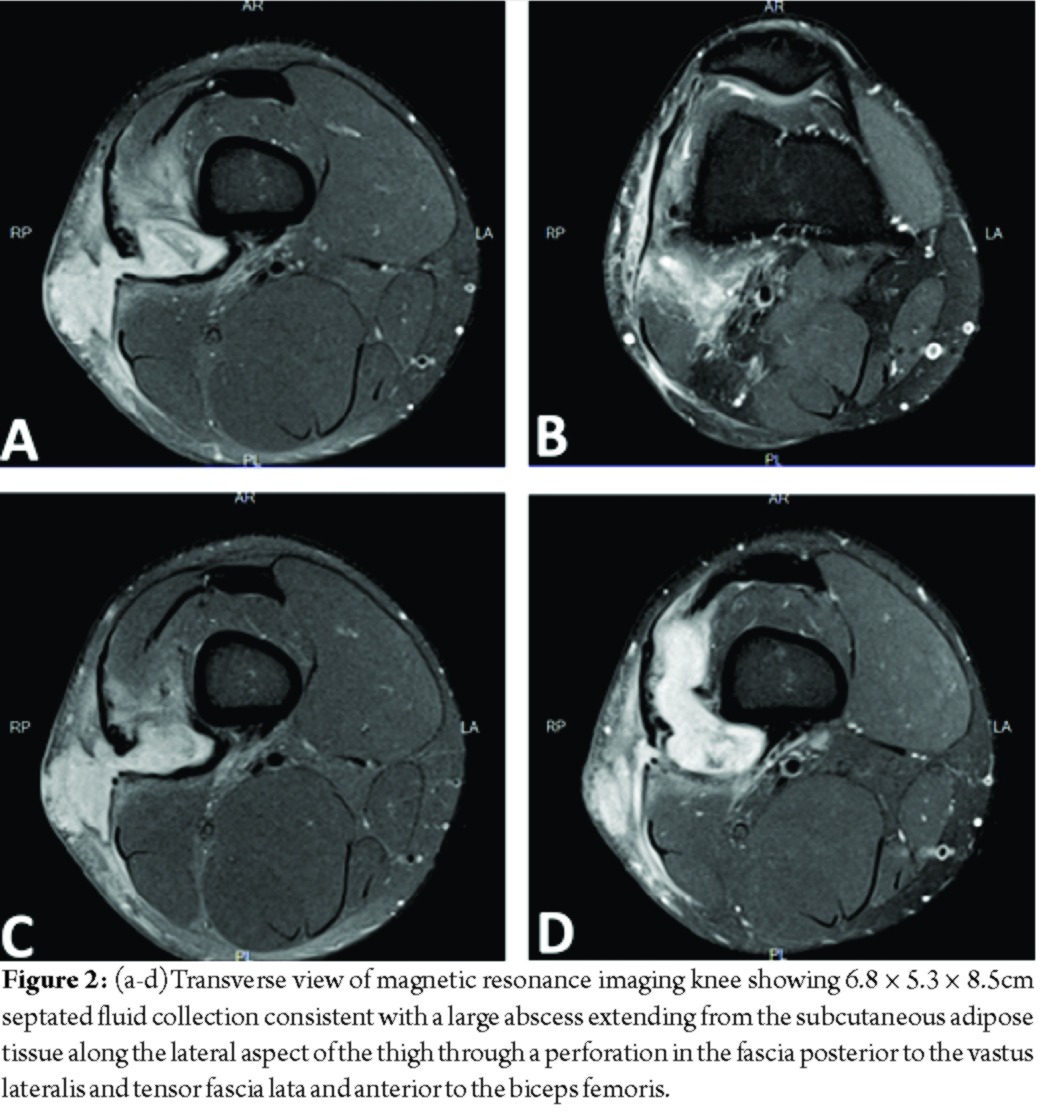

At presentation, the patient stated that this episode did not resolve with rest or anti-inflammatory medication. He reported the drainage had been ongoing for 2 weeks and appeared to come from a punctum in the center of the swelling, but denied any fever, chills, sharp pain, change in sensation, or restriction in active or passive range of motion. X-ray showed no acute OM or fractures (Fig. 1a and b). Magnetic resonance imaging (MRI) of the knee revealed 6.8 × 5.3 × 8.5cm septated fluid collection consistent with a large abscess extending from the subcutaneous adipose tissue along the lateral aspect of the thigh through a perforation in the fascia posterior to the vastus lateralis and tensor fascia lata and anterior to the biceps femoris (Fig. 2a-d). The fluid collection also extended deep between the muscle bellies to the level of the posterior lateral cortex of the distal femoral diaphysis. Diffuse soft-tissue edema was visualized; however, no periosteal or marrow edema was present, confirming the absence of acute OM (Fig. 3a and b).